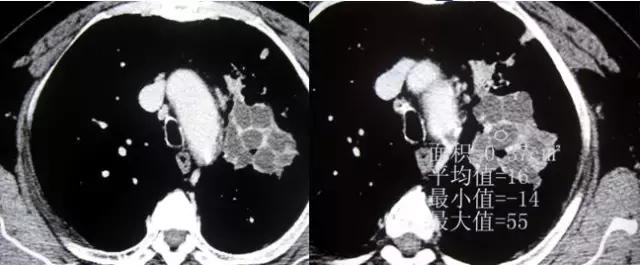

附:支气管粘液嵌塞

粘液支气管征或支气管粘液嵌塞:是因为扩张的支气管腔内分泌粘液无法排出或近端梗阻而郁积等原因所致。

CT表现:表现为分支状或指状致密影,呈指套征或“V”、 “Y”形征。

意义:表明有支气管扩张分泌粘液,支气管近端有梗阻粘液不能排出而郁积以及支气管闭索等。

分析考虑:扩张的支气管充满粘液呈纵行束状排列